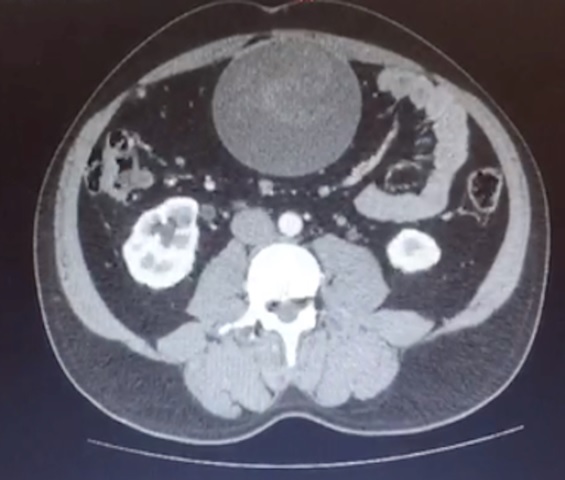

We present the case of a 42-year-old patient, who underwent an emergency laparotomy cholecystectomy 3 years ago, who consulted for a pain-free, progressing growth-free one-year central-abdominal tumor with no changes in transits. It is intra-abdominal, rounded 10 cm in diameter. A tomographic study was requested to confirm the finding, and the exploration was decided by means of a laparotomy that confirmed the presence of a surgical pad.